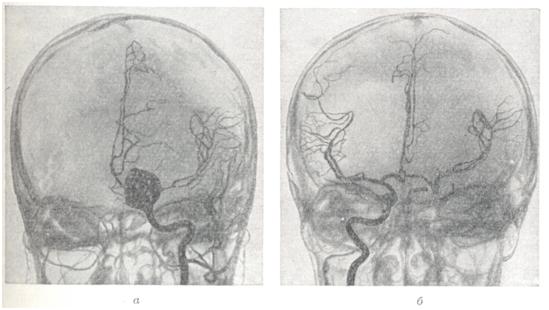

Рис. 5.

Ангиограмма больного после эмболизации большой артерио-венозной аневризмы бассейна средней мозговой артерии эмболами, часть из которых маркирована клипсами (указаны стрелками). Слева — ангиограмма больного до операции.

Рис. 6.

Ангиограмма больного после выключения из кровообращения артерио-венозной аневризмы бассейна средней мозговой артерии путем внутренней окклюзии приводящей артерии. Операция осуществлена с помощью сбрасывающегося баллончика (обозначен стрелкой). Слева — ангиограмма больного до операции.